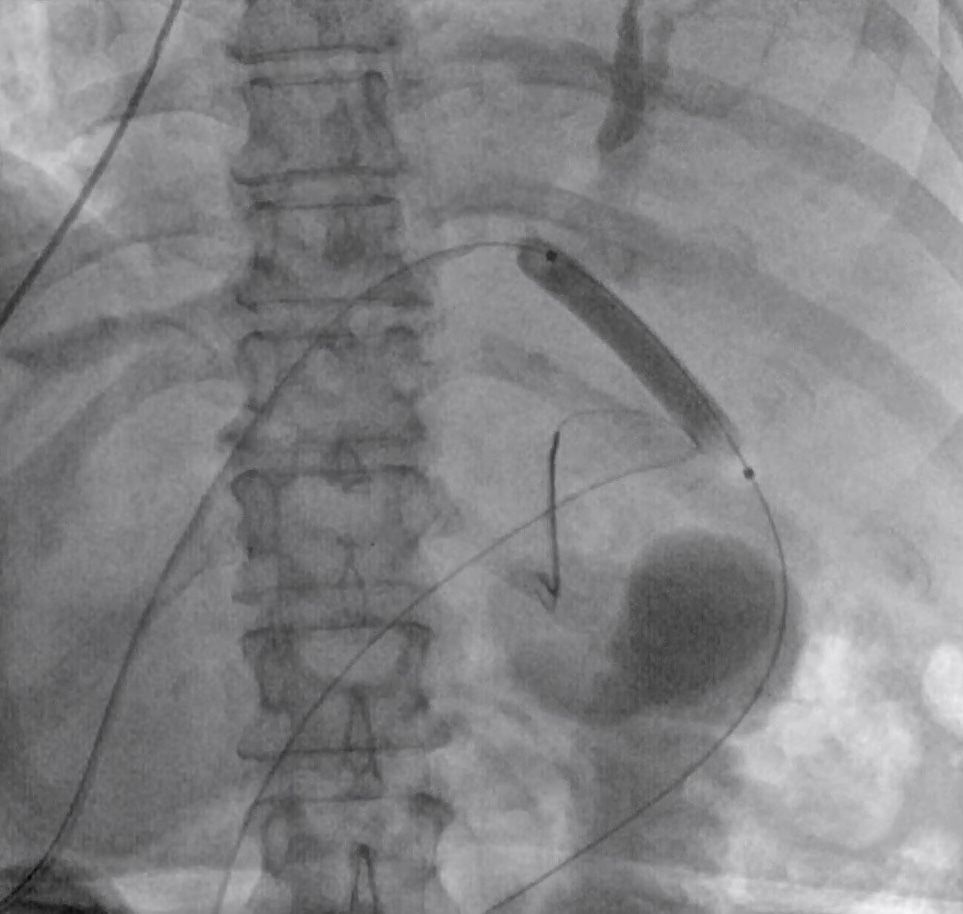

70 years old male, presented with Gastric Outlet Obstruction due to growth at the junction of D1 and D2. An ERCP was attempted, but an adult and pediatric duodenoscope could not be negotiated beyond growth, hence EUS-guided biliary drainage and enteral stent placement was planned